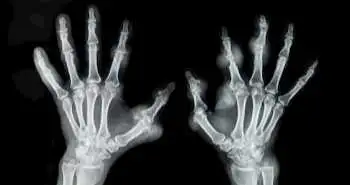

Використання ПЕТ / КТ з фторидом натрію F-18 для оцінки активності ревматоїдного артриту

У пацієнтів з діагностованим ревматоїдним артритом (РА) і синовіїтом зазначалося більш інтенсивне поглинання фториду натрію F-18 (NaF) суглобами в порівнянні з суглобами без синовіїту. Таким чином, встановлена ​​ефективність використання методів позитронно-емісійної томографії / комп'ютерної томографії (ПЕТ / КТ) з F-18 NaF для візуалізації при проведенні оцінки активності РА.

У дослідженні взяли участь 17 пацієнтів з РА. Крім фізикального огляду, аналізу крові і ультразвукового дослідження, учасникам проводили ПЕТ / КТ з F-18 NaF. Для кожного з 28 хворобливих суглобів, оцінених за допомогою індексу активності захворювання на основі оцінки 28 суглобів з урахуванням рівня осідання еритроцитів (DAS28CRP), розрахували стандартизований рівень накопичення речовини суглобами, а також співвідношення поглинання речовини суглобом і кістковою тканиною.

У хворобливих суглобів з набряком і без нього стандартизований рівень накопичення (СРН) був статистично значимо вище, як і співвідношення поглинання речовини суглобом і кістковою тканиною, в порівнянні з суглобами без синовіїту (див. таблицю нижче).

Згідно стандартизованого рівня накопичення суглобами, чутливість методу при прогнозуванні синовіїту склала 83,2%, а специфічність - 92,7%, в той час як для співвідношення поглинання речовини суглобами і кістковою тканиною чутливість і специфічність склали 81,5% і 90,7% відповідно. Сукупність обох обстежень ПЕТ / КТ 28 суглобів виявила 100% діагностичну точність щодо високої активності РА.